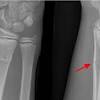

How Long Does It Take For A Fracture To Heal - Stress fracture is the name given to a pathological condition in which there is development of tiny cracks in the bones.

Took seven years to for stress fracture in hip to heal completely. It takes roughly six to eight weeks for a stress fracture to heal. 'how long before a fracture heals?' bydaryl rosenbaum, m.d., director, sports medicine fellowship. Stress fracture is the name given to a pathological condition in which there is development of tiny cracks in the bones. The majority of hairline fractures will heal by themselves if the person refrains from activities that strain the affected area. This is typical for most men and women; Sometimes stress fractures take a little bit longer to heal. To answer the question about the time taken for a stress fracture to heal, in majority of cases it usually takes around 6 to 8 weeks for the stress fracture to fully heal. In fact there were two fractures in the same area. Scapular body fractures are typically treated nonsurgically with good results. Metacarpal fractures usually take about six to eight weeks to heal. A fracture caused by a disease or condition is known as a pathological fracture. It take about 6 to 8 weeks to heal.